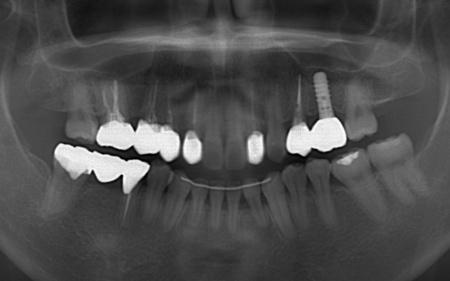

| カウンセリング | 拝見したところ、左下と右上の歯はともに大きな虫歯があり、歯だけでなく被せ物を支える土台の部分にも影響が及んでいました。

さらに、ほかの歯に入っている詰め物や被せ物の周囲にも、過去に治療した部分に再び虫歯ができる二次カリエスが複数見つかりました。 また、噛み合わせを確認したところ、奥歯で噛み合わせた際に上下の前歯が当たらず隙間ができる開咬(かいこう)が認められました。 実際に患者様の場合も、特定の歯に長期間強い力がかかり続けたことで歯や修復物の破損、さらには口腔内全体のトラブルにつながった可能性が高いと考えられました。 修復治療が必要でしたがこの噛み合わせの問題を改善しないまま行うと、治療した歯に再び過度な力が加わって被せ物の破損・脱離や虫歯の再発を招くリスクが高まります。 |

| 治療内容 |

まずは矯正治療を優先し、噛み合わせが整ってから虫歯の再発リスクの低いセラミックの被せ物・詰め物などで歯の形態と機能を回復する方針を提案し、同意いただきました。

矯正治療については、専門的な診断と管理が必要と判断したため専門の矯正歯科医院をご紹介し、他院にて実施していただきました。 矯正治療終了後、改めてお口の中を確認したうえで、歯の状態に合わせ虫歯の除去や土台の修復を丁寧に行い、精密な型取りを実施しています。 最後に噛み合わせ全体のバランスを確認しながら新しく作製した被せ物や詰め物を装着し、見た目に問題がないか、噛み合わせが安定しているかを確認し、治療を終了しました。 |